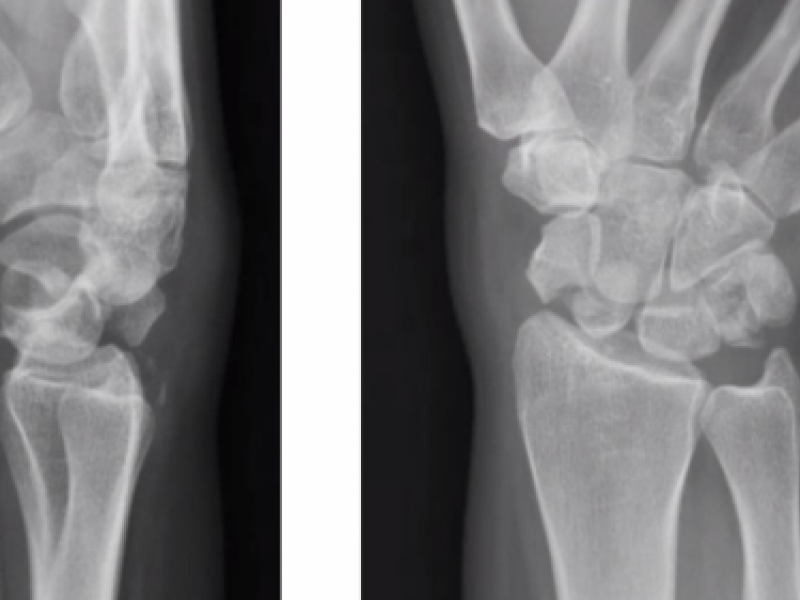

Wrist dislocations

Perilunate dislocation Scaphoid fracture Triquetrum fracture